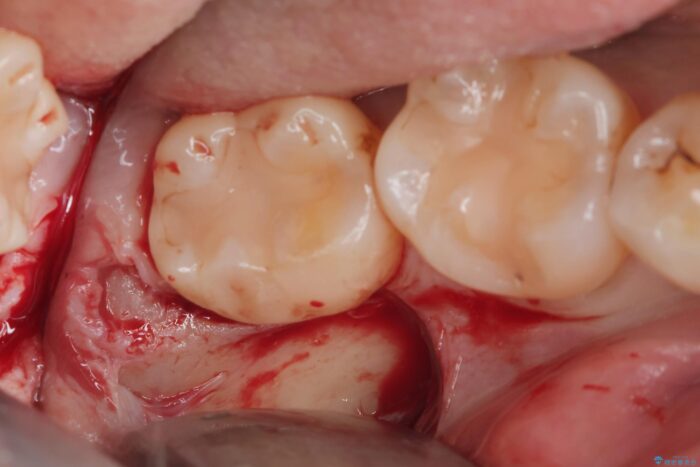

埋伏歯の抜歯

埋まっている親知らずを抜歯したいとご来院されました。

パノラマ,CT撮影を行い安全なことを確認して抜歯を行いました。